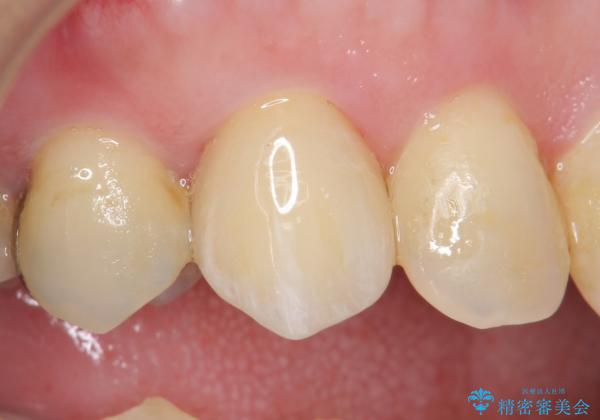

再根管治療を行い症状が治まったのを確認後、オールセラミッククラウン(スペシャル)による補綴を行いました。

前歯の補綴ではオールセラミッククラウンを希望される患者様が多いですが、オールセラミッククラウンの中でも、エコノミー、スタンダード、スペシャル、エクセレントとランクがあります。

その中でも特に審美性が高いのがスペシャル、エクセレントです。スペシャル、エクセレントは口腔内写真をもとに熟練の技工士が、患者様の口腔内に合わせたオーダーメイドのクラウンを製作致します。